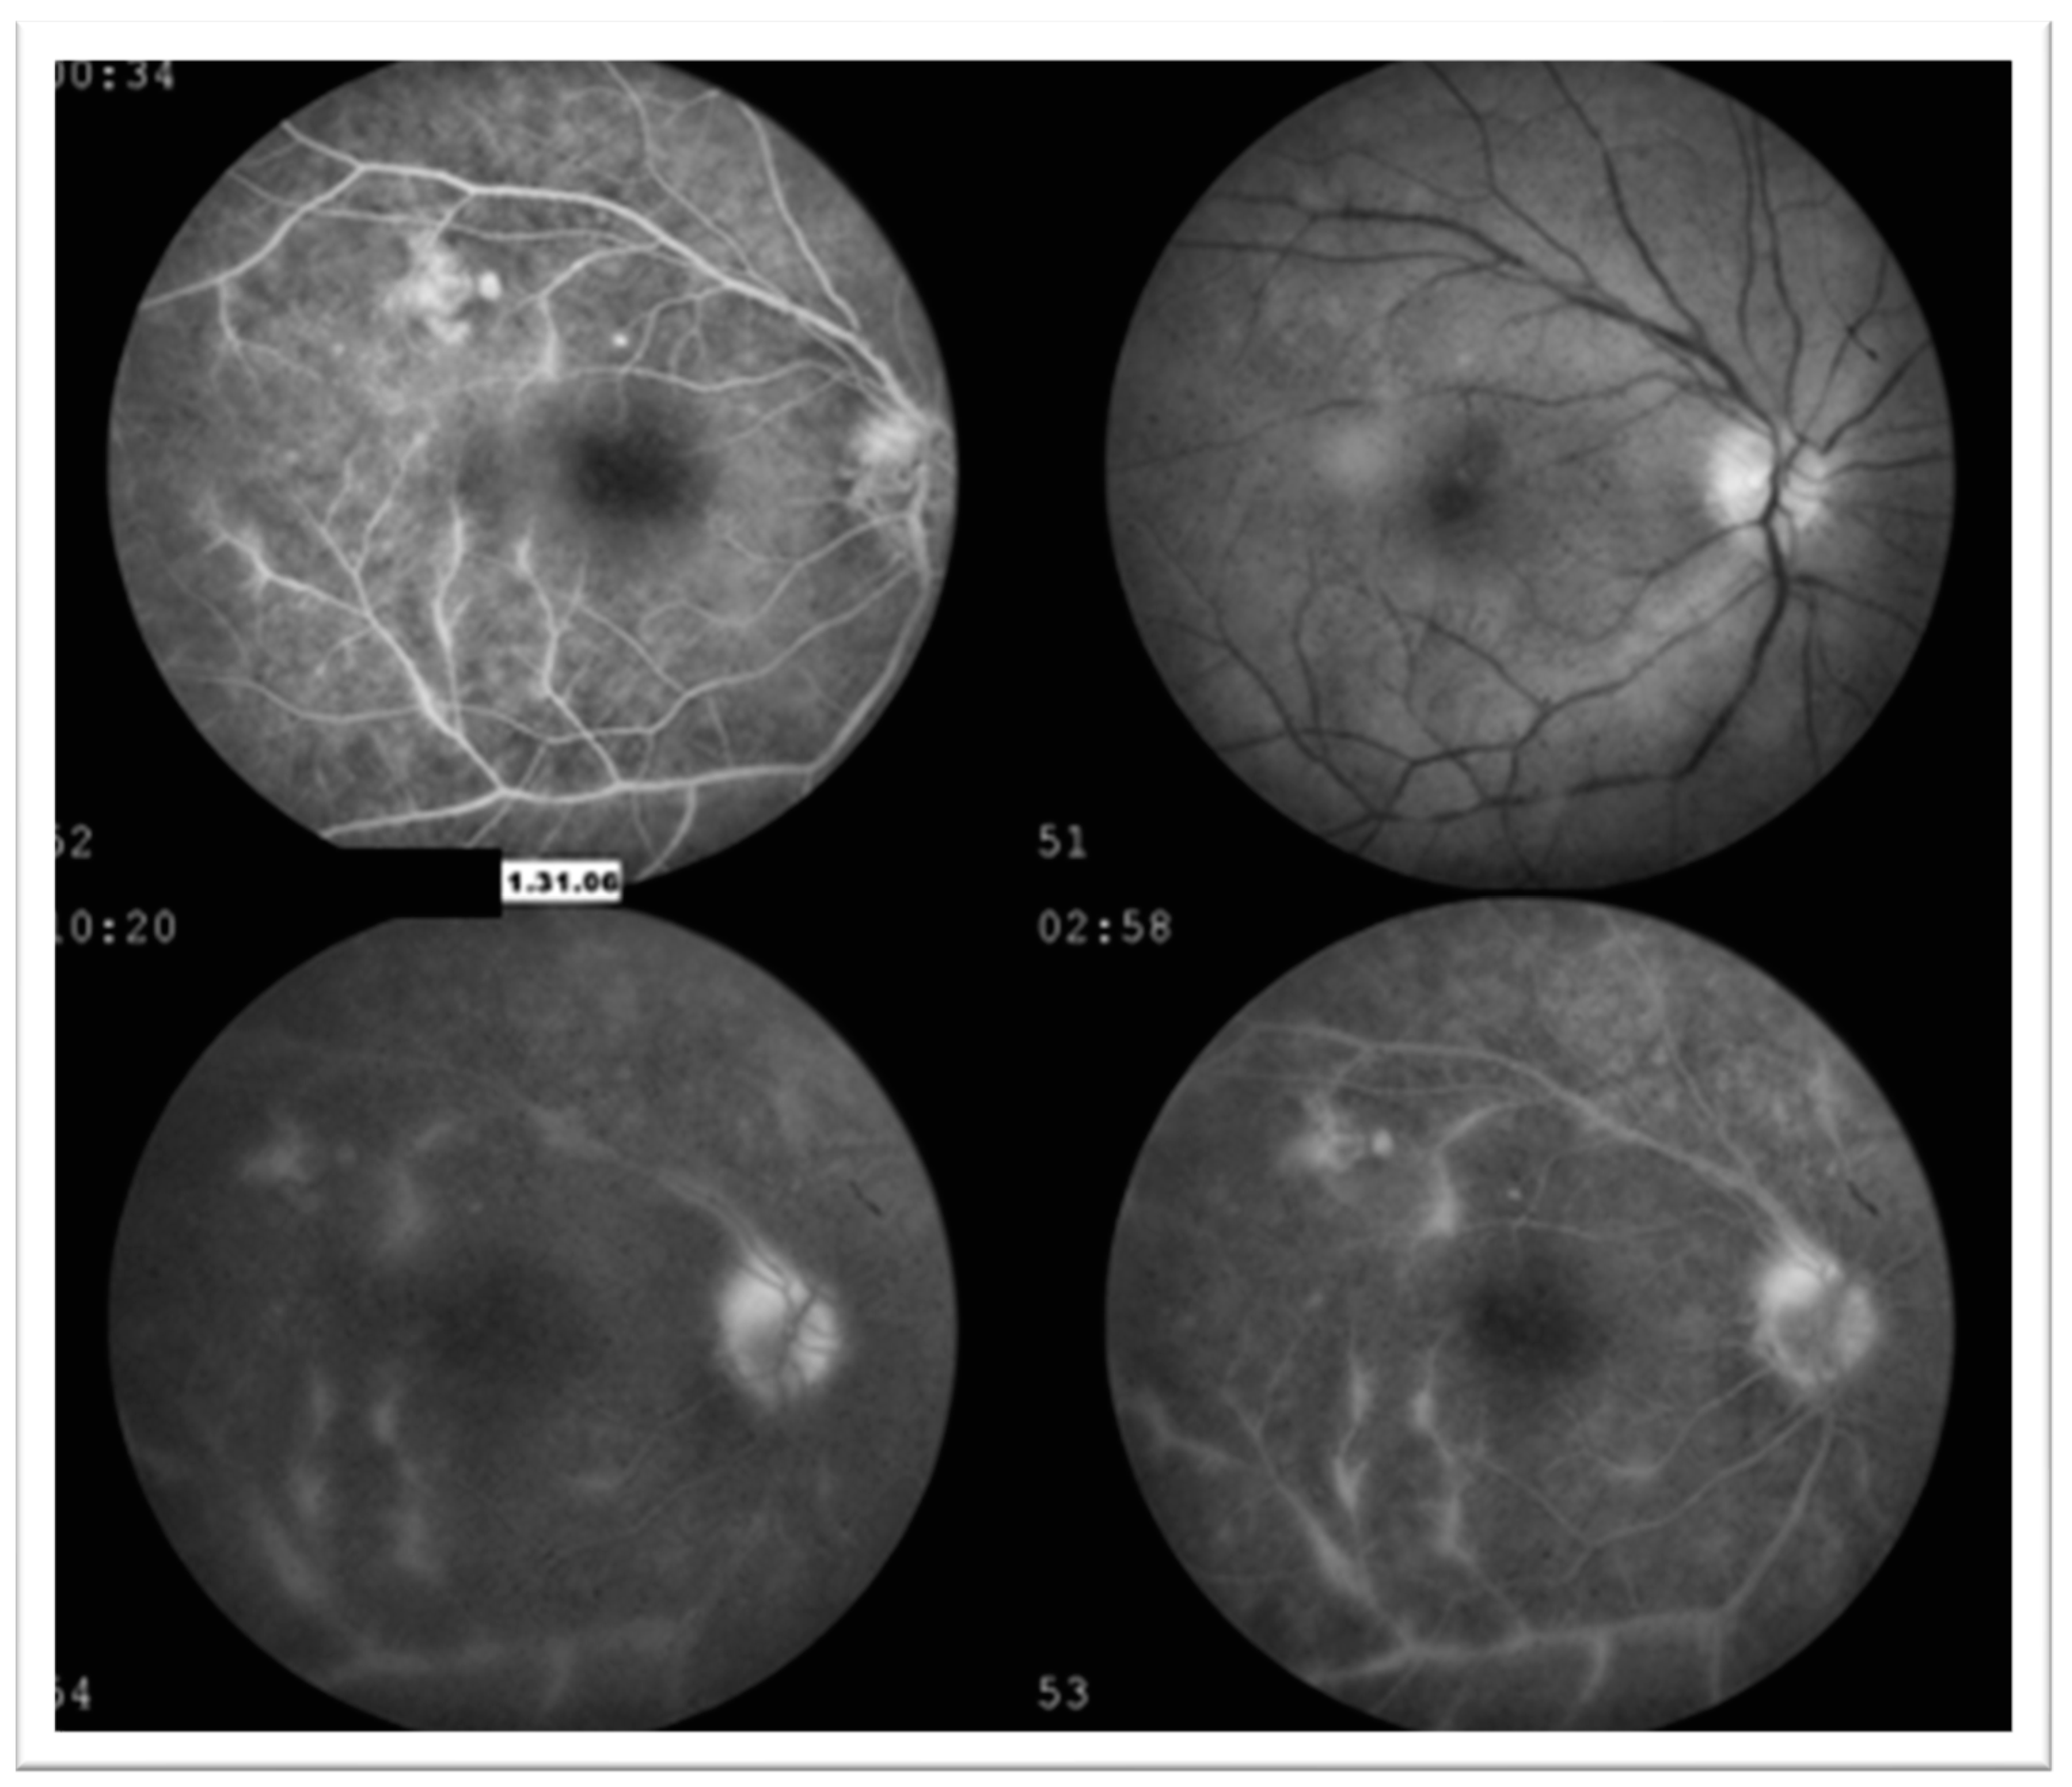

3.2. Case 2: 45-Year-Old Female with Recurrent Anterior Uveitis and Retinal Vasculitis